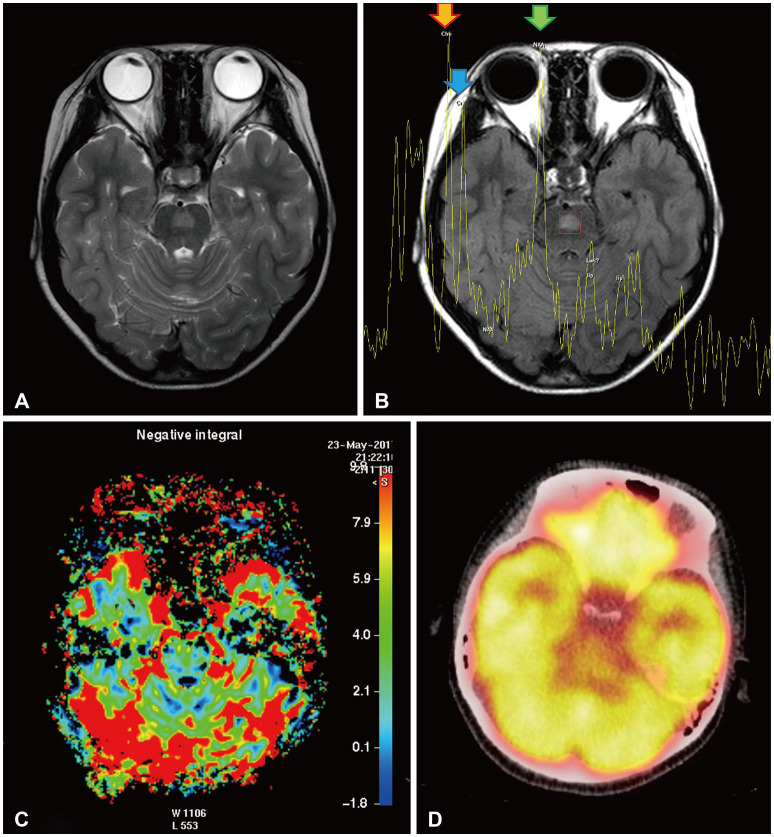

Differential diagnosis of focal brainstem lesions detected on MRI is challenging, especially in young children. Formerly, brainstem gliomas were classified mainly based on MRI features and location. However, since 2016, the World Health Organization's brainstem lesion classification requires tissue biopsy to reveal molecular characteristics. Although modern techniques of stereotactic or navigation-guided biopsy ensure accurate biopsy of the lesion with safety, biopsy of brainstem lesions is still generally not performed. Here, we report a focal brainstem lesion mimicking brainstem glioma in a 9-year-old girl. Initial MRI, MR spectroscopy, and 11C-methionine positron emission tomography (PET) features suggested low-grade glioma or diffuse intrinsic pontine glioma. However, repeated MR spectroscopy, perfusion MRI, and 18fluorodeoxyglucose PET findings suggested that it was more likely a non-tumorous lesion. As the patient presented not with a neurological manifestation but with precocious puberty, the attending oncologist chose to observe with regular follow-up MRI. The pontine lesion with high signal intensity on T2-weighted MRI regressed from the 6-month follow-up and became invisible on the 1.5-year follow-up MRI. We reviewed brainstem glioma-mimicking lesions in the literature and discussed the key points of differential diagnosis.